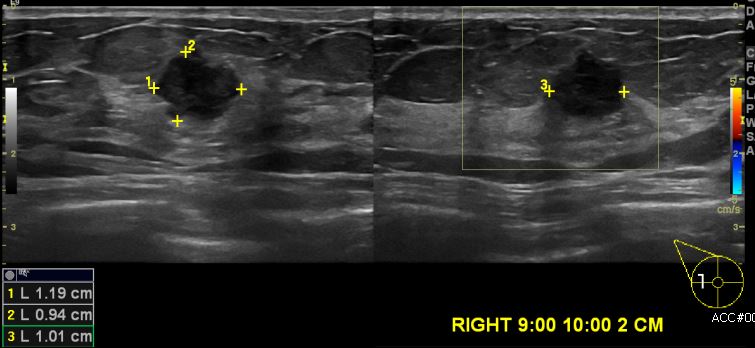

우측 유방에 만져지는 멍울로 내원하신 50대 여성분으로 본원 초음파상 우측

9시에서 10시 방향 2cm 떨어진 거리의 멍울 조직검사 시향하여 우측 침윤성 유관암

진단되었습니다.